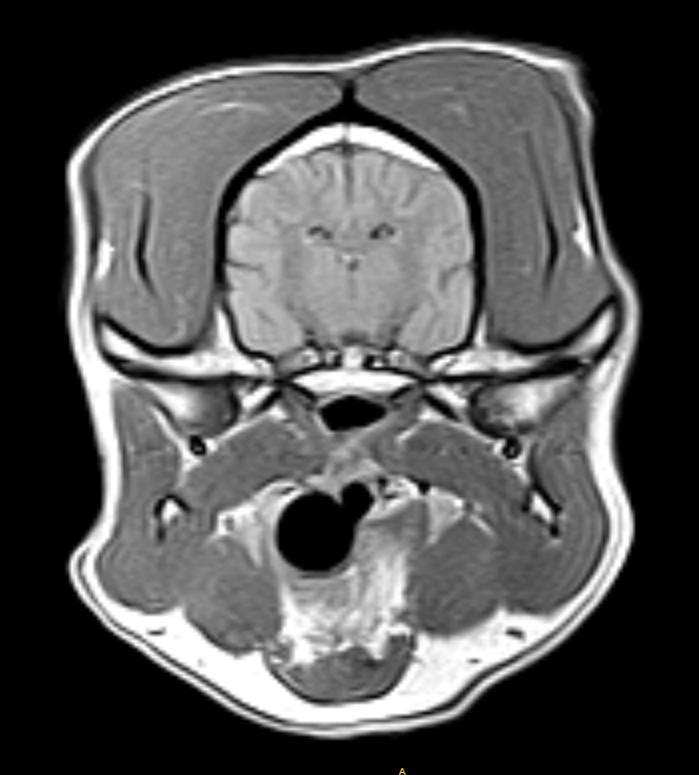

IMÁGENES CLÍNICAS

En la sección de imágenes clínicas, destacamos la precisión y claridad de nuestros estudios, respaldados por un equipo de radiólogos especializados en medicina veterinaria. Nos enorgullece ser un aliado confiable para veterinarios y clínicas, brindando un servicio rápido y eficiente para ayudar en la toma de decisiones clínicas fundamentadas.

Utilizamos resonancia magnética para obtener imágenes detalladas de tejidos blandos, articulaciones y el sistema nervioso central, permitiendo diagnósticos más precisos.